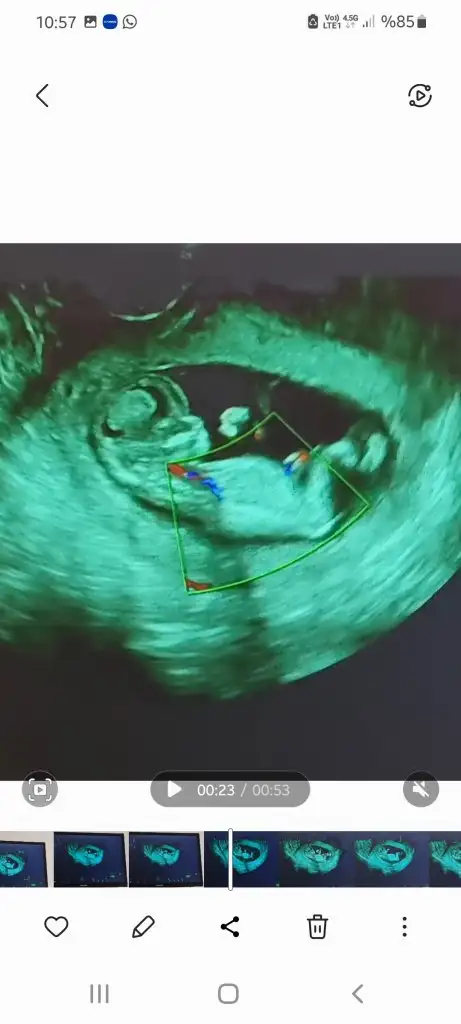

6+3 karından kuzum 😍 ayy bakayım ne çıkacak

• 33261C6B-ACDD-43F9-BD4E-F272EB65229F.webp

33261C6B-ACDD-43F9-BD4E-F272EB65229F.webp

27,5 KB · Görüntüleme: 216